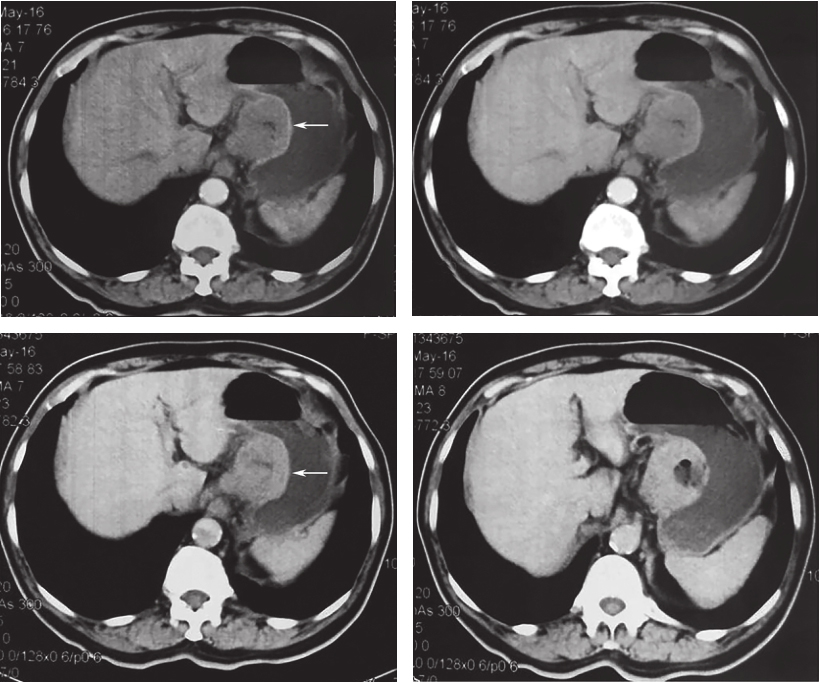

外院上下腹增强CT:胃小弯侧GIST可能(3.5cm×3.2cm),伴周围淋巴结肿大,胆囊结石,胆囊炎(图1)。

图1腹部CT见胃小弯软组织团块